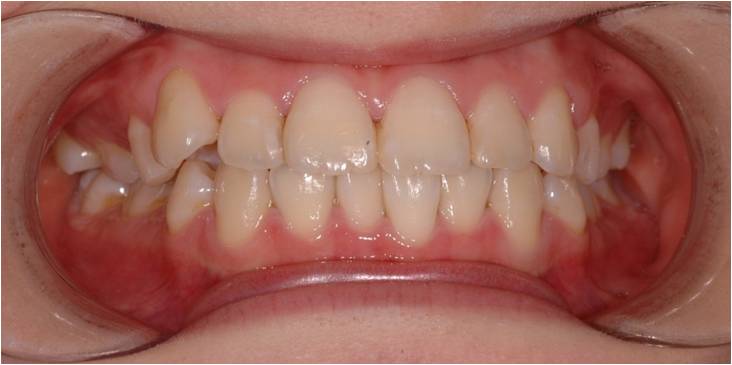

설측교정장치

치아 안쪽에 장치를 붙여 겉으로는 전혀 보이지 않는 장치입니다.